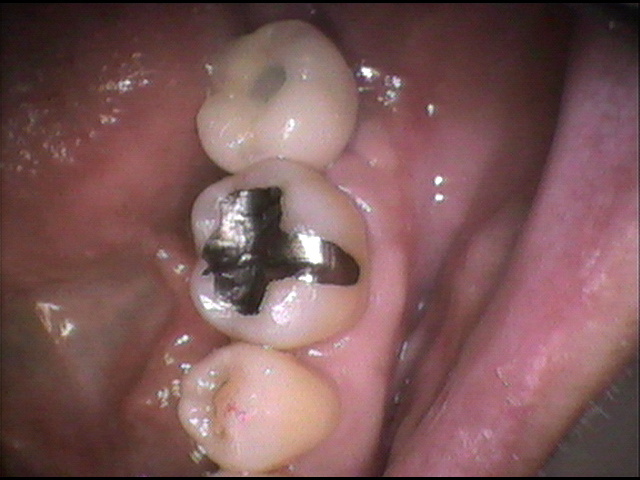

- 術後の口腔内写真です。

あまりインプランとは目立たない様に植立されています。

患者さんも、普通に噛める様になって喜ばれていました。